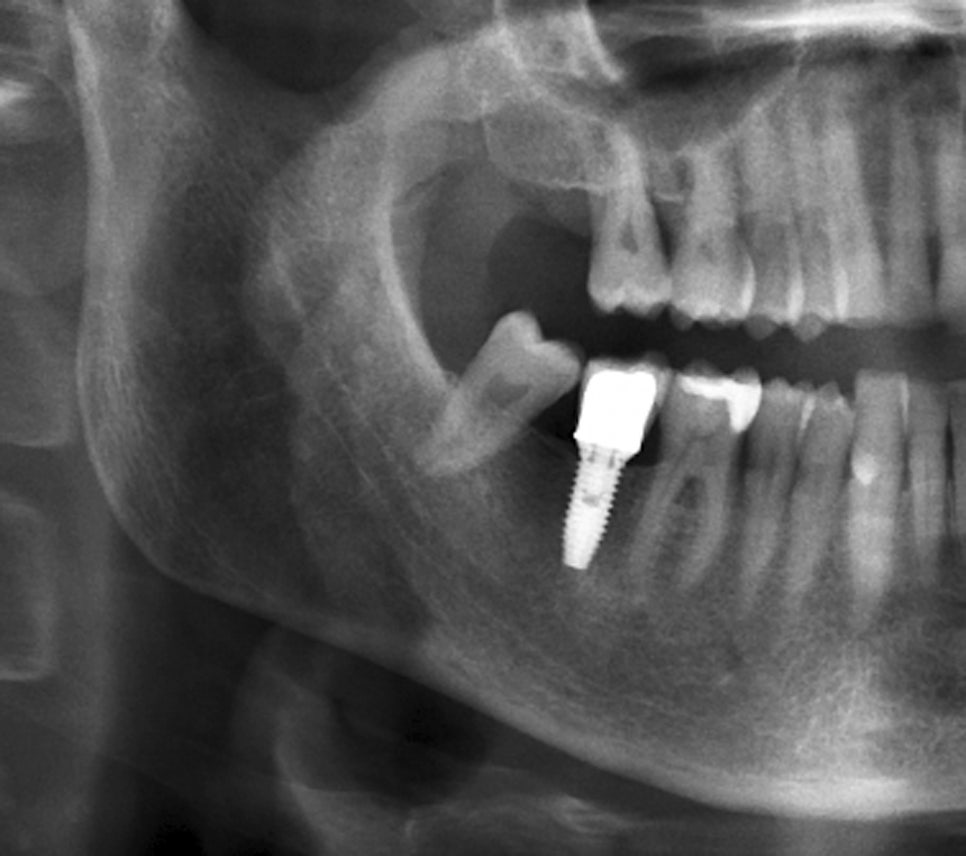

이해를 돕기 위한 예시 이미지입니다

임플란트 재수술 전

3D CT 디지털 장비를 통해

눈에 보이지 않는 실패 원인까지

다각도로 분석하여

'두 번의 실패 없는' 계획을 세웁니다.